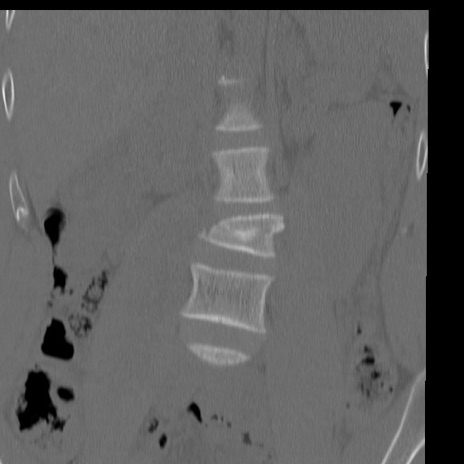

症例3 腰椎CT(冠状断像)

腰椎CT

矢状断像